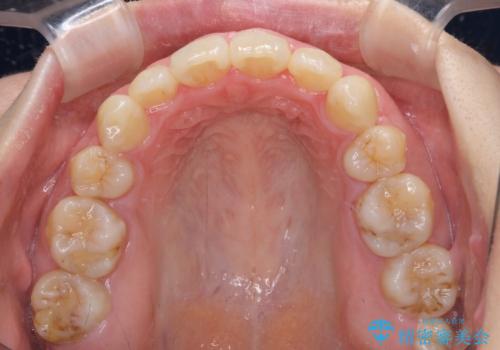

インビザラインによる矯正治療は、どれだけマウスピースを外す時間を短くできるかが成功の鍵となりますが、抜歯矯正ではよりシビアに要求されます。

こちらの患者様は、1日22時間以上を厳守してくださり、3年強で終えることができました。